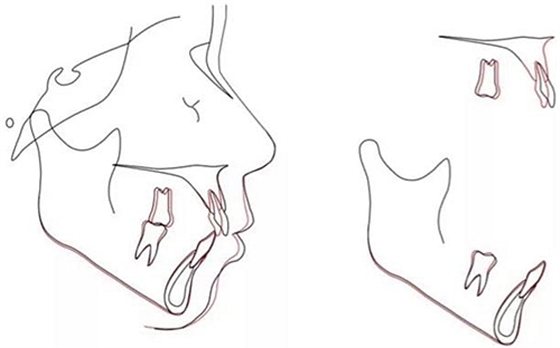

該患者在6顆上前牙區(qū)使用雙J鉤片段弓,水平臂均用0.028-in不銹鋼絲制成,作用力在臂的最末端,力的模擬見圖4。使用該方法能夠模擬正畸時受到的力。文獻(xiàn)表明,TAD深度8mm為佳,前牙阻抗中心由牙齒移動模式?jīng)Q定水平臂的末端而決定。圖4顯示了6顆前牙在內(nèi)收4mm后牙周膜的應(yīng)力分布。當(dāng)力的延長線通過6顆牙的阻抗中心是,牙齒整體移動且壓低0.5mm,當(dāng)其處于阻抗中心冠方時,前牙舌傾,當(dāng)其處于根方時,根舌向移動。(圖5)

治療后頭側(cè)數(shù)據(jù)提示:無明顯骨性變化(上頜SNA82.1°,下頜SNB74.9°),上頜前牙得到內(nèi)收,略舌傾,頦部前后位置無明顯改變,仍未凸面型(圖8,表)。將治療前后圖像重疊后結(jié)果如(圖8及圖9),24月后隨訪結(jié)果見圖10.